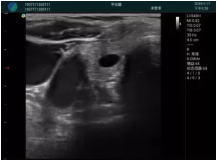

清晰顯示腺體內(nèi)低回聲快影,邊界清晰,包膜較光滑

確定進針路徑并實時監(jiān)測抽吸針與腫塊位置關(guān)系

抽吸針進入腫塊內(nèi)部進行旋切

抽吸過程中可見腫塊明顯縮小,并根據(jù)腫塊位置改變針道位置

抽吸旋切后再進行超聲復(fù)查,原腫塊區(qū)域未見殘留組織及出血